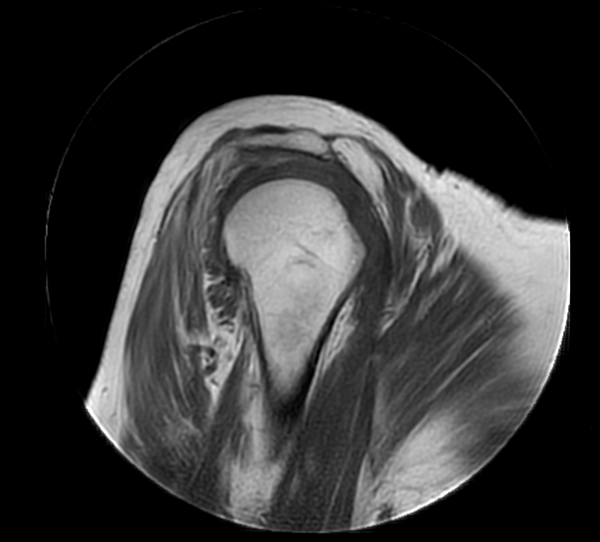

Coronal MultiVane XD - T2w TSE